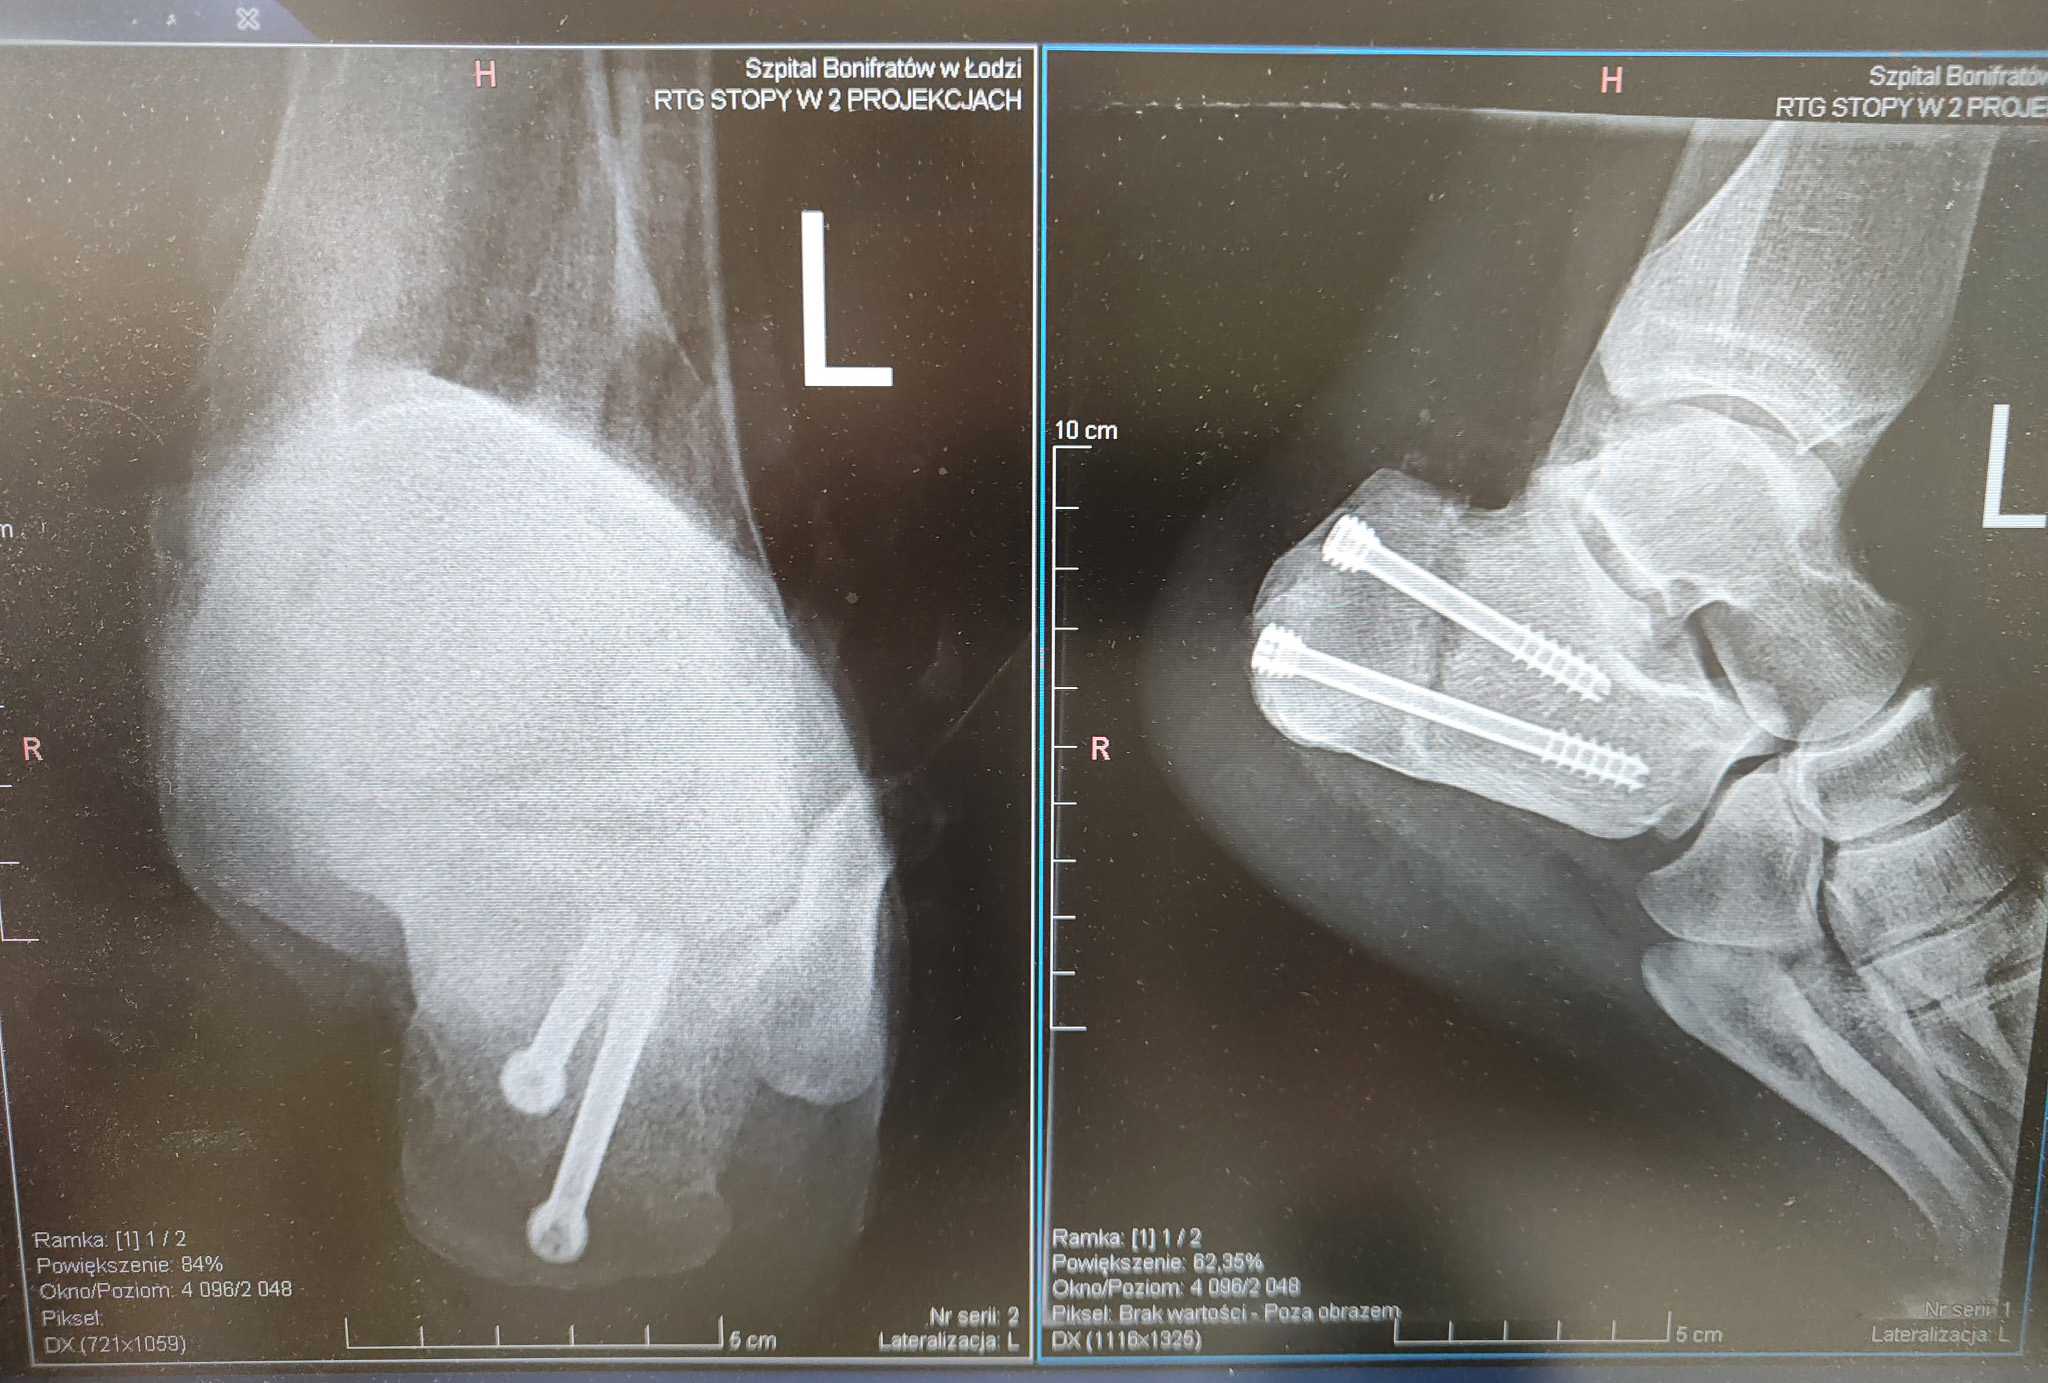

Osteotomia wg Zadecka to zabieg operacyjny stosowany w leczeniu przewlekłego zapalenia przyczepu ścięgna Achillesa. Polega na wykonaniu kontrolowanego przecięcia (osteotomii) kości piętowej w taki sposób, aby zmienić ustawienie guza piętowego względem ścięgna Achillesa. Zmiana kąta przyczepu ścięgna powoduje zmniejszenie napięcia oraz ograniczenie drażnienia tkanek w miejscu przyczepu, co prowadzi wraz z plastyką tkanek miękkich do redukcji bólu i poprawy funkcji stopy.

- Osteotomia zamykająca – dzięki temu fragmenty kości dobrze do siebie przylegają, co sprzyja szybkiemu zrostowi.

- Stabilne zespolenie wewnętrzne (najczęściej przy użyciu śrub) zapewnia odpowiednią stabilność po zabiegu.